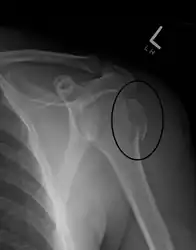

A fracture of the greater tuberosity as seen on AP X ray

A fracture of the greater tuberosity of the humerus